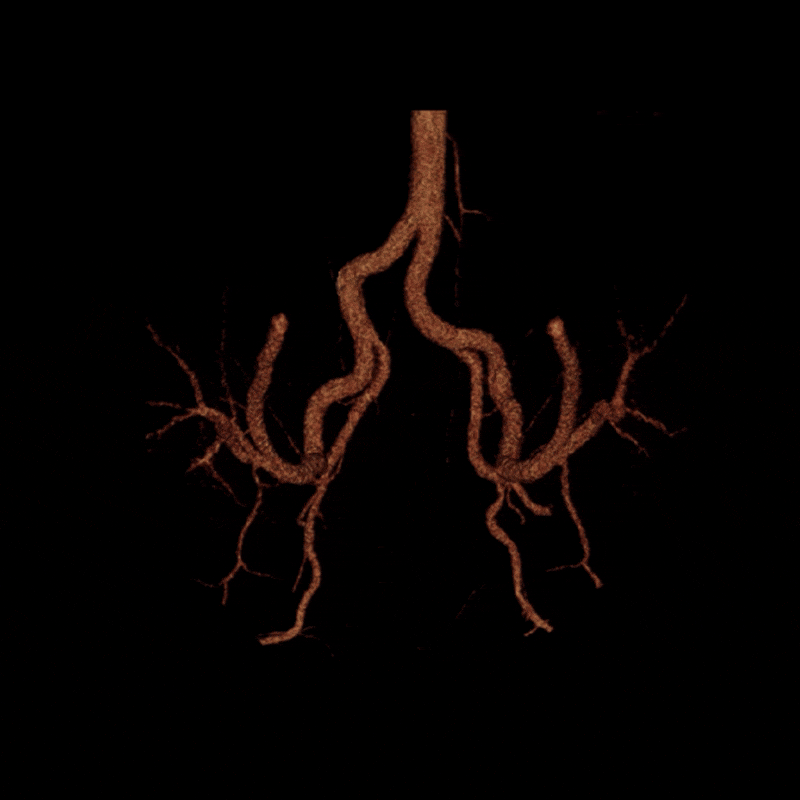

A dynamic CTA was performed in both relaxed and stressed (flexed) positions to simulate the limb posture during activity. Changes in hip and pelvic motion can alter the course of the external iliac artery, and narrowing that affects blood flow may appear only when the limb is under tension. Imaging at rest alone may overlook these positional changes, so evaluating both postures helps determine whether the symptoms are related to dynamic vessel deformation rather than fixed structural disease. (Learn about a similar condition, popliteal entrapment, here).

To better visualize the iliac anatomy, CPR loops were created to trace the artery along its course in both relaxed and stressed positions, allowing direct comparison of lumen size and curvature. VR views were generated with and without pelvic and femoral bone to show surrounding anatomical relationships. These complementary views help clarify how limb motion influences vessel shape and highlight narrowing that may be subtle or difficult to appreciate on axial slices alone. (Learn more about CPRs here, and VRs here).

When the patient moved into the stressed position, the right external iliac artery showed two areas of luminal narrowing (a temporary decrease in the size of the vessel’s opening). One narrowing was more proximal (closer to the vessel’s origin near the pelvis) at about ten to twenty percent, and the second was more distal (farther along the vessel toward the leg) at about thirty to forty percent. Both returned to a widely patent appearance (fully open) when the leg moved back to a relaxed position.

The left external iliac artery remained patent across positions, and the common iliac arteries were tortuous (naturally curving) without any fixed stenosis. This pattern aligns with external iliac endofibrosis, where motion causes the artery to change shape rather than a fixed obstruction, highlighting why positional imaging can reveal abnormalities that may not appear on routine resting studies.